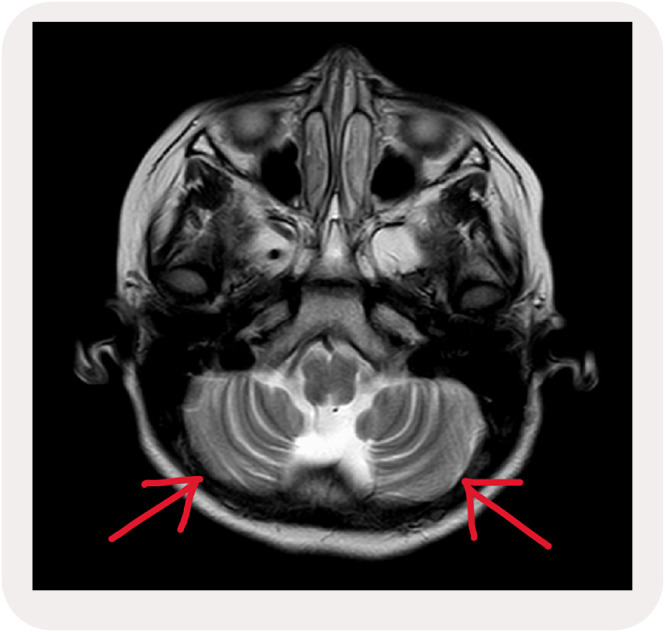

Ataxia telangiectasia (AT) is a rare neurodegenerative condition with a prevalence of 1 in 40,000 to 1 in 300,000 worldwide. It involves a genetic mutation of chromosome 11q.26. The condition is inherited in an autosomal recessive manner causing atrophy of the cerebellum due to loss of Purkinje fibres. AT presents early in childhood and the clinical features depend on the type of mutation. The study is a case report of a rare genetic disorder of a 9-year-old female who came to the physiotherapy clinic with a diagnosis of AT. The patient was presented with progressively worsening gait problems with frequent falls, with complete dependence on assistance and impaired balance and coordination. The treatment program was 12 months divided into an intense physiotherapy program for two months followed by 10 months of two times per week of physiotherapy sessions. The program was divided into four elements which are: (1) Lifestyle changes, (2) Strengthening exercises, (3) Coordination exercises, and (4) Balance training exercises. The result showed a positive outcome in increasing the patient's independence, increased muscle strength, reduced ataxia symptoms intensity, and the patient can carry out complex activities with the help of accessory orthosis devices.